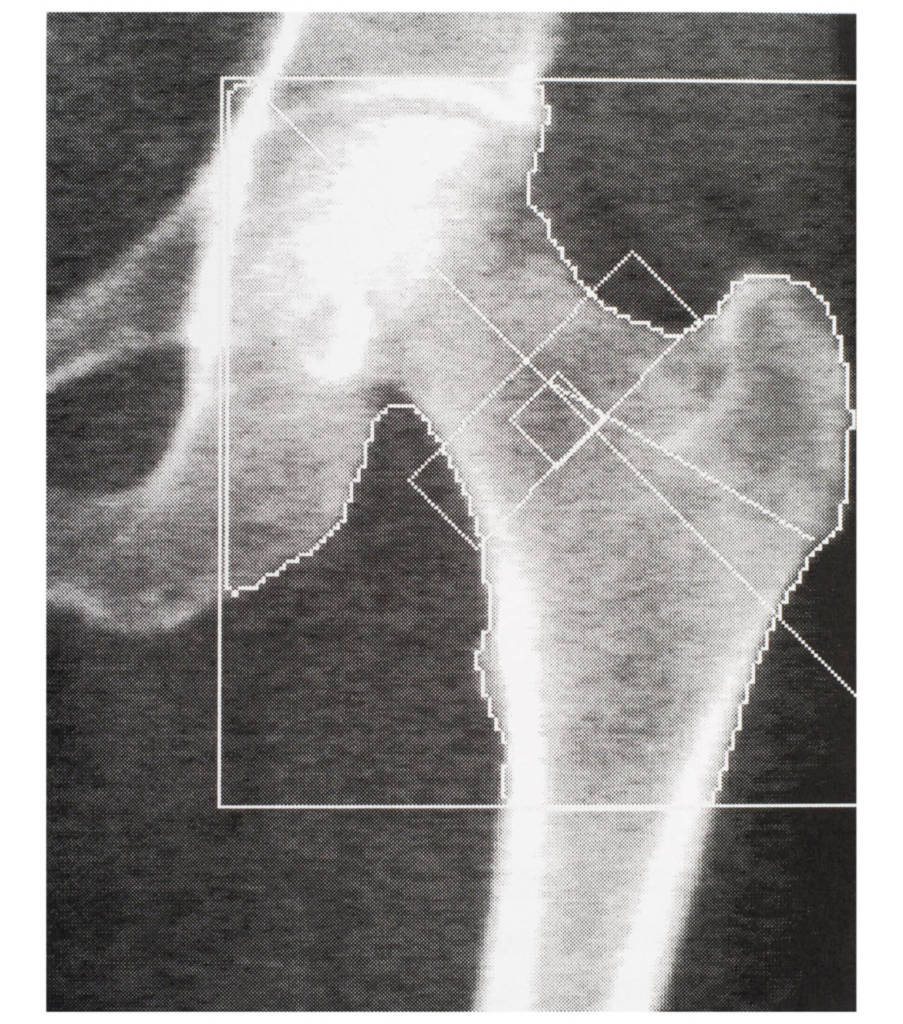

Per scoprire se si è a rischio di questo problema occorre quindi misurare la propria densità ossea stabilendo così se il livello è normale oppure no. E l’unico esame in grado di misurare con precisione la densità ossea e di effettuare la diagnosi precoce dell’osteoporosi, secondo l’Organizzazione Mondiale della Sanità, è proprio la Mineralometria Ossea Computerizzata, che da adesso abbrevieremo in MOC, considerata la metodica di riferimento.